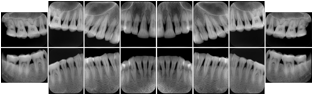

3. A dental provider wishes to capture a series of DICOM IO images for the patient’s dentition. The tooth morphology, teeth are divided into molars, premolars, canines and incisors, and a number of images for each jaw. The anatomic information was captured utilizing the triplet of schema. This standard code sequence is based on ISO 3950-2010, Dentistry - Designation system for teeth and areas of the oral cavity.

Every IO image should have anatomic information either through the primary or modifier sequence.

In most standard cases, images are oriented in structured layouts. These structured displays are useful to be shared between providers for reference purposes.

Table OO.1.1-1 shows structured display standard templates, where Viewset ID is based on the Japanese Society for Oral and Maxillofacial Radiology (JSOMR) classification provided by JIRA (Japan Medical Imaging and Radiological Systems Industries Association, www.jira-net.or.jp). Expected or typical teeth to be imaged location, region and designation codes are based on ISO 3950-2010, Dentistry - Designation system for teeth and areas of the oral cavity. For all the hanging protocols listed in OO.1.1-1, the value to use for Hanging Protocol Creator (0072,0008) is "JSOMR" and the value to use for Hanging Protocol Name (0072,0002) does not include "JSOMR" (e.g., "DL-S001A", not "JSOMR DL-S001A").